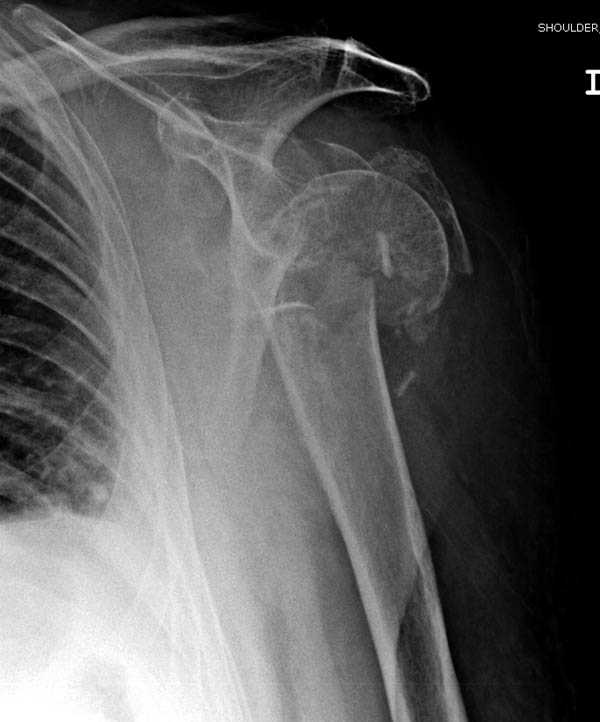

Пациентка Б.1953 г.р., врач-терапевт. Травма 27.11.08г. Падение с высоты роста. Выявлен закрытый не осложненный оскольчатый перелом хирургической шейки левого плеча со смещением. 02.12.08г. оперирована. Выполнена открытая репозиция и остеосинтез пластиной LCP Деост с дополнительной фиксацией отдельно лежащего фрагмента винтом. Послеоперационный период протекал без особенностей, заживление раны первичным натяжением. Швы сняты через 10 дней. Иммобилизация левой верхней конечности клиновидной подушкой 4 недели. По окончании срока – рентген-контроль и умеренная разработка плечевого сустава. В течении месяца функция левого плечевого сустава восстановилась удовлетворительно: поднятие руки до 110 гр., отведение - 90 гр. и до 110 гр. отведение с лопаткой. Отведение руки назад – 20 гр. Наружная и внутренняя ротация – 20 гр. Пациентка по настоянию самостоятельно вышла на работу. 27.03.09 при контрольном осмотре жалоб не предъявляет, болевой синдром в левом плечевом суставе отсутствует. Отведение плеча активно до 90 гр, пассивно с лопаткой до 110 гр., поднятие – 110 гр, отведение назад 20 гр, наружная и внутренняя ротация по 20 гр. На контрольных рентгенограммах отмечается смещение металлоконструкции, ротация головки плеча с приведением дистального отломка на 13 гр. и смещением к зади на 30 гр. Рентгенограммы прилагаются. Ваш взгляд на дальнейшую тактику лечения пациентки?

Уважаемый Евгений, похоже, что первый и второй Р-снимки выполнены несколько в разных положениях(ротация) плечевой кости, в связи с этим создается впечатление смещения пластины. Остеосинтез выполнен при угловом смещении отломков.Таковым и остался. Данная ситуация была бы очевидна гораздо раньше, если бы при контрольной Р-графии были выполнены снимки в 2-х проекциях.(Не в обиду, сам иногда выполняю только один).

Здесь пример открытой репозиции 57 летнего с переломом плеча (1,2) смещение обнаружено на интероперационном снимке. При нормальной прямой проекция (3) угловое смещение обнаружили в аксиальной проекции (4)